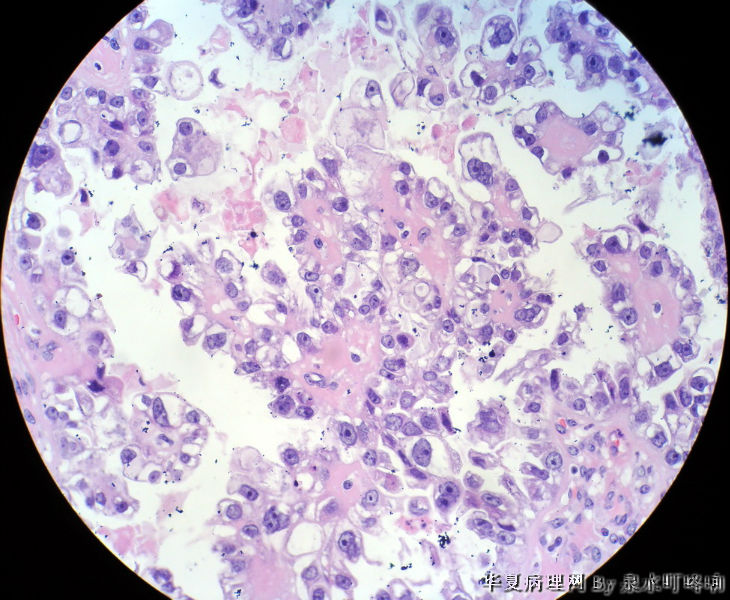

左卵巢肿物

左卵巢肿物图2

名称:图2

描述:2

天津肿瘤医院会诊:混合细胞上皮癌(透明细胞癌+浆液性囊腺瘤+勃勒那氏瘤)。

女,42岁,左卵巢肿物。

大体,灰褐色囊性肿物一个,大小约13×9×8厘米,临床已切开,内容物流失,肿物内壁可见多发乳头,最大4×3×3厘米,小者如绿豆大。